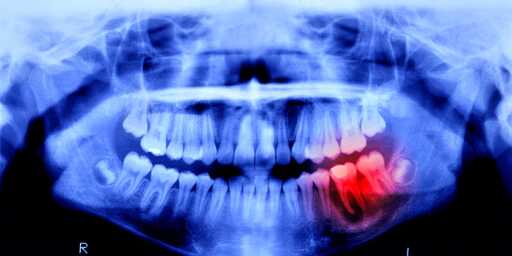

This is my main concern. I will believe they can regrow lost teeth, but can they regrow them in the correct shape and location? Teeth can take some weird shapes. We’ve got millions of years of evolution tweaking exactly where and how they grow, and it still goes wrong sometimes. I suspect messing with that process can lead to Cronenbergian results.

A tooth infection can easily spread to your brain and kill you. It’s a very short path.

Gum disease has been linked to heart disease and now there might be a link to dementia due to the bacteria that can enter the bloodstream from the mouth.